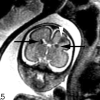

Fetal MR imaging is an increasingly available technique used to evaluate the fetal brain and spine. This is made possible by recent advances in technology, such as rapid pulse sequences, parallel imaging and advances in coil design. This provides a unique opportunity to evaluate processes that cannot be approached by any other current imaging technique and affords a unique opportunity for studying in vivo brain development and early diagnosis of congenital abnormalities inadequately visualized or undetectable by prenatal sonography. This 2-part review summarizes some of the latest developments in MR imaging of the fetal brain and spine and its application to prenatal diagnosis. This first part discusses the utility, safety, and technical aspects of fetal MR imaging, the appearance of normal fetal brain development, and the role of fetal MR imaging in the evaluation of fetal ventriculomegaly. The second part focuses on additional clinical applications of fetal MR imaging, including suspected abnormalities of the corpus callosum, malformations of cortical development, and spine abnormalities.